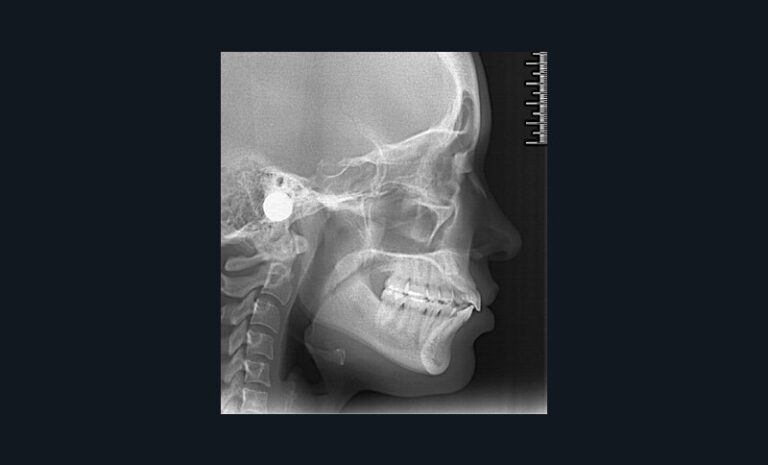

Dans l’exemple (fig. 1 et 2), la patiente présente une classe 1 molaire et classe 2 canine bilatérale sur un schéma normodivergent de classe 2 squelettique associé à une biproversion incisive et la canine 23 incluse.